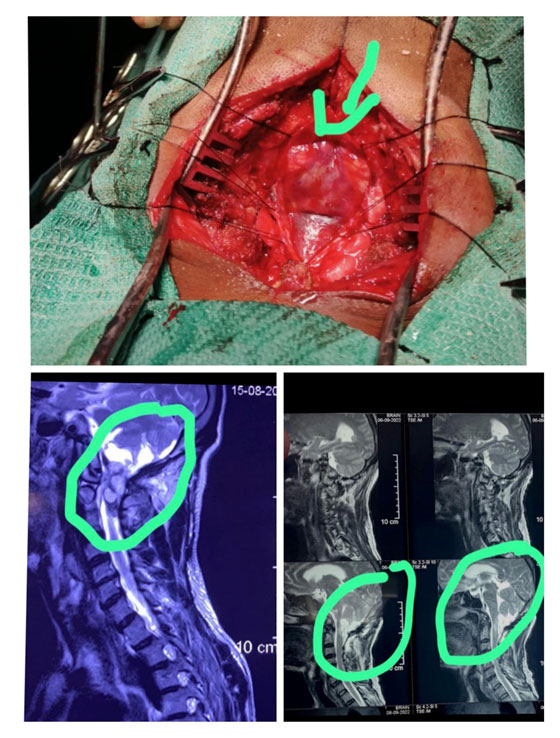

2.CVJ ANAMOLIES

Case Of CVJ Anamoly